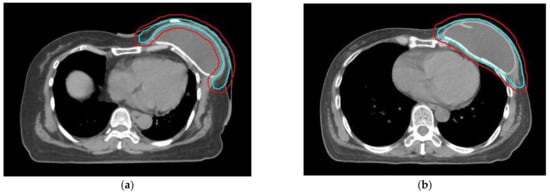

2.2. RT Treatment Plan